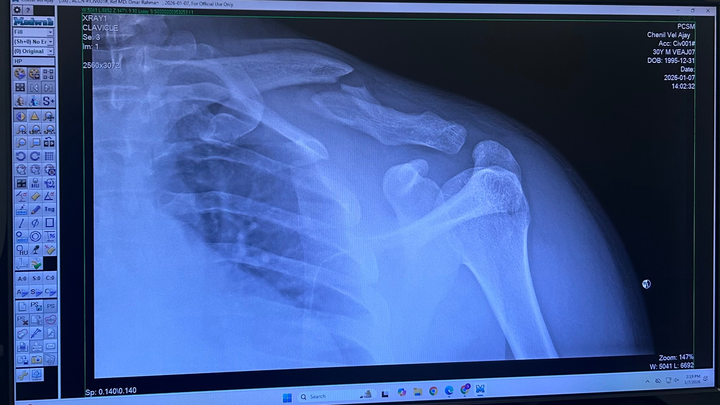

On December 29th, my life took an unexpected turn when I was hit by a car while riding a Lime scooter. The accident left me with a broken clavicle and significant bruising on my hips and legs. As a result, I need surgery on my collar bone and have been unable to attend work. Not having health insurance has made this situation even more challenging, as the medical bills and daily living expenses are quickly adding up.